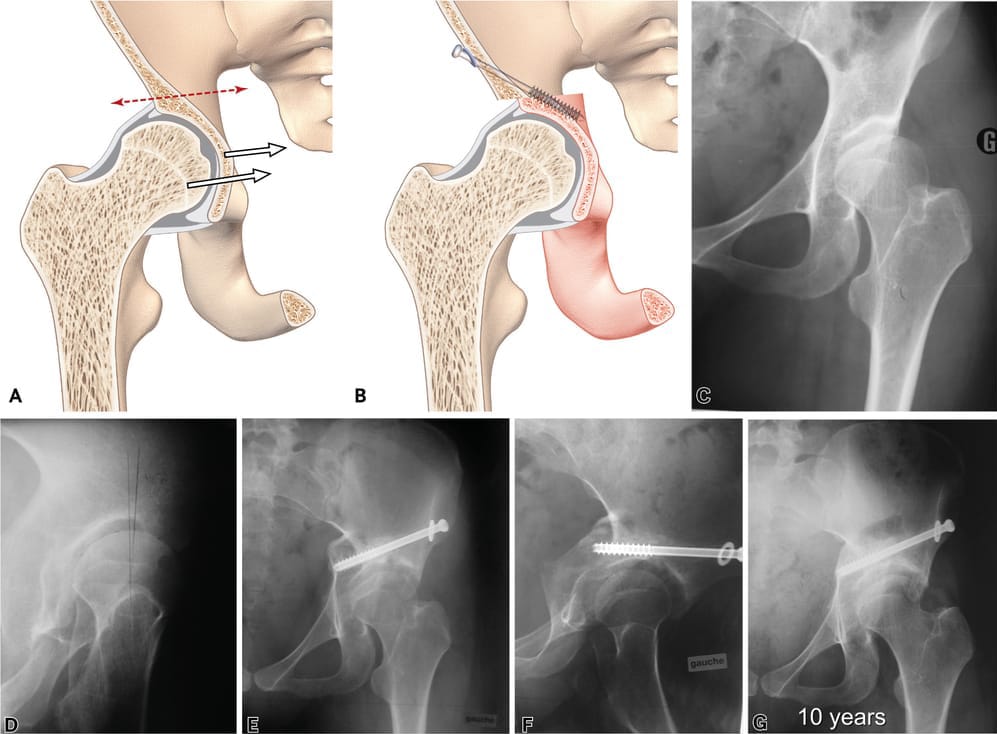

Chiari osteotomy

The Chiari osteotomy was described in 1953. This is an extra-articular dome osteotomy [8], Migaud H, Chantelot C, Giraud F, Fontaine C, Duquennoy A. Long-term survivorship of hip shelf arthroplasty and Chiari osteotomy in adults. Clin Orthop Relat Res. 2004 Jan;(418):81–6. https://doi.org/10.1097/00003086-200401000-00014[9], Chiari K. Medial displacement osteotomy of the pelvis. Clin Orthop Relat Res. 1974 Jan-Feb;(98):55-71. doi: 10.1097/00003086-197401000-00008. PMID: 4817245.[10] Chiari C, Schneider E, Stamm T, Peloschek P, Kotz R, Windhager R. Ultra-long-term results of the Chiari pelvic osteotomy in hip dysplasia patients: a minimum of thirty-five years follow-up. Int Orthop. 2024 Jan;48(1):291-299. doi: 10.1007/s00264-023-05912-9. https://doi.org/10.1007/s00264-023-05912-9 that follows the contour of the femoral head to medialise the centre of rotation of the joint and increase the acetabular surface (Figure 7). As with the bone block, this osteotomy above the acetabulum uses capsular metaplasia with fibrocartilaginous tissue, but the medialisation produced decreases the lever arm of the joint and therefore intra-articular stresses.

This strategy usually begins with the Smith–Petersen approach and a single osteotomy incision above the acetabulum, oriented cranially from the outside inwards under fluoroscopic guidance, and following the contour of the femoral head. At the planning stage, it is important to make sure that the osteotomy will end below the sacroiliac joint, or it will not be possible to mobilise the distal fragment. The new positioning is achieved by placement in abduction and fixation with a 6.5mm screw. The main complications described, though certainly rare, are nerve damage (sciatic nerve) and non-union. Functional outcomes are good, with survivorship over 70% after 15 years (74–97%), 60–85.9% after 30 years and 35% survivorship after 40 years in Chiari’s original series. This technique is not especially sensitive to deformity of the femoral head, subluxation or osteoarthritis if dysplasia is severe with negative VCE and VCA (< 0°) (Figure 8).